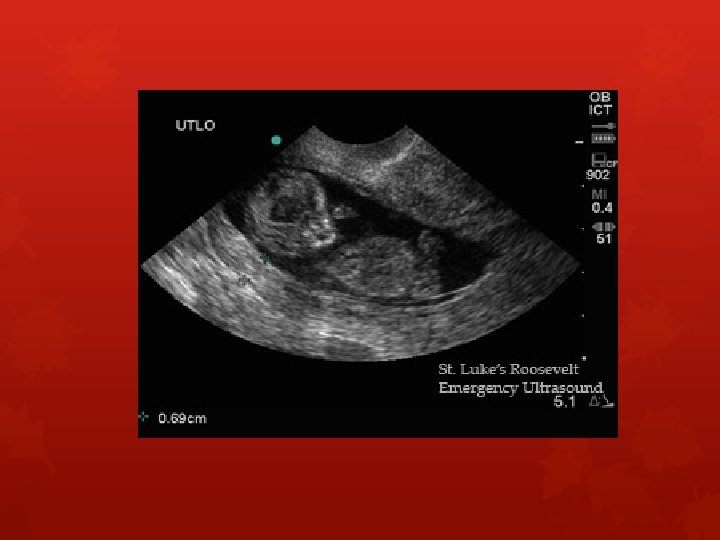

Hydrops Fetalis A condition in the fetus characterized by an accumulation of fluid or edema in at least 2 fetal compartments: (i. e. , abdomen, lungs, heart muscle). Subcutaneous tissue/scalp pleura (pleural effusion) pericardium (pericardial effusion) Abdomen (ascites) OR Skin edema and fluid in ONE body cavity.

Hydrops fetalis is a condition in the fetus characterized by an accumulation of fluid, or edema, in at least two fetal compartments, including the subcutaneous tissue, pleura, pericardium, or in the abdomen, which is also known as ascites. The edema is usually seen in the fetal subcutaneous tissue, sometimes leading to spontaneous abortion. It is a prenatal form of heart failure, in which the heart is unable to satisfy the insatiable demand for an unusually high amount of blood flow. Hydrops fetalis (ie, fetal hydrops) may also be associated with polyhydramnios and placental edema.

There can be skin edema and fluid in more than 2 body cavities in its most severe form. NOTE: normal skin thickness is 1 -2 mm ANASARCA-also known as extreme generalized edema is a medical condition characterized by widespread swelling of the skin due to effusion of fluid into the extracellular spaces. HALO sign refers to edema around the fetal head. Edema past the calvaria causes a double ring-very poor prognosis.